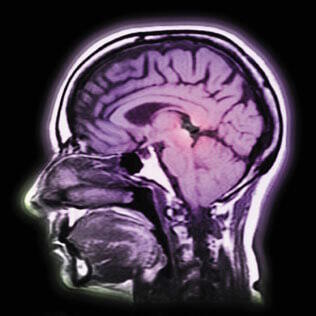

Le 5-HTP est une substance naturelle que l'on extrait des graines d'une plante médicinale d'Afrique de l'Ouest, Griffonia simplicifolia. Chez l'homme, le 5-HTP est un nutriment précurseur immédiat d'un neurotransmetteur, la sérotonine. En d'autres termes, il est directement converti dans le cerveau en sérotonine. Une supplémentation en 5-HTP peut restaurer les niveaux de sérotonine et aider à améliorer l'humeur générale, la dépression, l'anxiété, l'insomnie, la perte de poids, les maux de tête chroniques ou la fibromyalgie.

La sérotonine, la dopamine et la noradrénaline sont les trois principaux neurotransmetteurs “monoamines”. Mono, parce que chacun d'eux est fabriqué à partir d'un acide aminé spécifique. La sérotonine est produite à partir du tryptophane alors que la dopamine et la noradrénaline le sont à partir de la tyrosine et de la phénylalanine. La barrière hémato-encéphalique empêchant la sérotonine d'être “importée” de l'extérieur du cerveau, toute la sérotonine utilisée par les cellules cérébrale doit être fabriquée à l'intérieur des neurones. Normalement, la barrière hémato-encéphalique est un moyen d'empêcher les toxines d'entrer dans le cerveau. Mais cette protection est telle que même des molécules “amies” comme des acides aminés nécessaires au cerveau sont arrêtées.

Lorsque des nutriments sont autorisés à traverser la barrière hémato-encéphalique, ils doivent être “portés” par des molécules de transport spécialisées tout comme des passagers doivent être transportés par un bus. La sérotonine elle-même ne peut pas traverser la barrière hémato-encéphalique alors que son précurseur, le tryptophane, doit partager son “bus” de transport avec cinq autres acides aminés, la leucine, l'isoleucine, la valine, la tyrosine et la phénylalanine. Ce qui limite encore ses chances de traverser avec succès.

Lorsque les neurones convertissent le tryptophane en sérotonine, ils doivent d'abord utiliser une enzyme dépendant de la vitamineB3 qui le transforme en 5-HTP. Une enzyme dépendant de la vitamineB6 est ensuite employée pour convertir le 5-HTP en sérotonine.

Un chercheur a souligné qu'il y a plusieurs avantages à considérer le 5-HTP plutôt que le L-tryptophane comme un élément déterminant permettant d'élever les niveaux de sérotonine. 5-HTP n'est pas dégradé par le tryptophane pyrrolase en kynurénine alors que c'est ce qui se passe avec 95% du tryptophane. De plus, 5-HTP traverse facilement la barrière hémato-encéphalique. Enfin, le 5-HTP n'est pas comme le tryptophane incorporé aux protéines, pas plus qu'il n'est utilisé pour fabriquer de la vitamineB3. Ainsi, si on le compare au tryptophane, on peut considérer que le 5-HTP est un véritable missile guidé, directement ciblé pour augmenter les niveaux cérébraux de sérotonine.